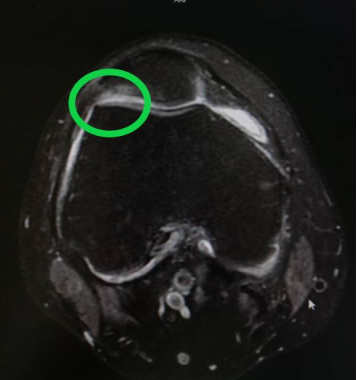

接诊的李亚楠医生详细询问了黄先生的病史 , 并对其进行了体格检查 , 发现其膝关节存在明显的髌骨摩擦感 。 结合其过往的工作经历和最近的运动史 , 李亚楠判断 , 黄先生出现的是“髌骨关节软骨软化” 。 之后进行的磁共振检查 , 证实了他的判断 。

圆圈内为髌股关节软骨磨损部位 。